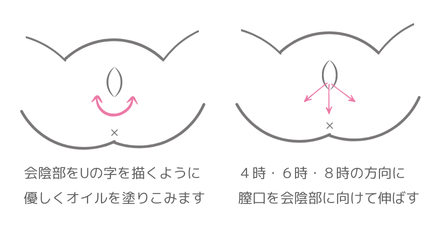

会陰切開の痛みや傷跡はどういうもの?AMOMA公式 母乳育児向け専門ハーブティー、アロマ、マッサージオイルAMOMA naturalcare通販サイト。

会陰切開今回は会陰切開の回復を早めるポイントをご紹介📢 "これからママになる 全ての女性をサポートしたい" そんな想いから 時期別 葉酸サプリmitas seriesシリーズは生まれました。  ̄ ̄ ̄ ̄ ̄ ̄ ̄ ̄ ̄ ̄ ̄ ̄ ̄ ̄ 妊活中に特化した温活もできるmitas妊娠中。